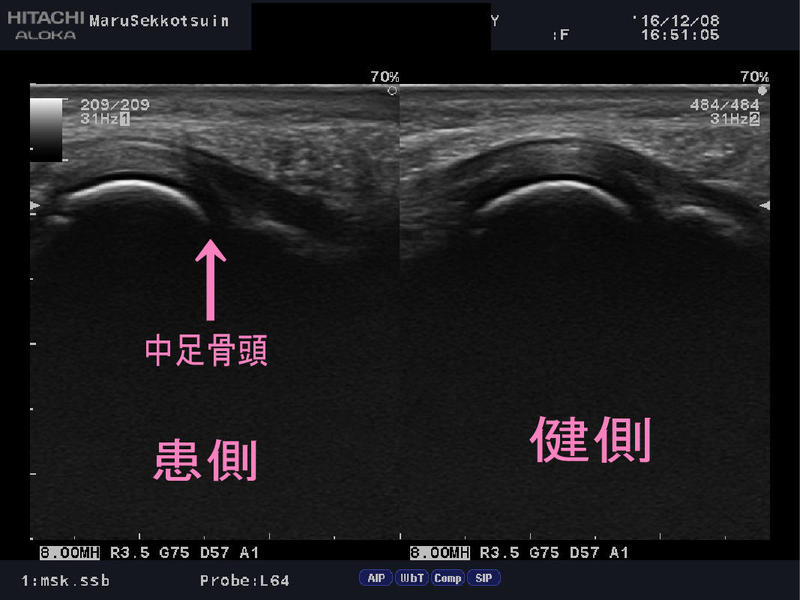

問診、触診後、思春期の女性に多い、

「Freiberg病(フライバーグ病)」「第2ケーラー病」という、

繰返し中足骨骨頭部に圧迫力が加わり、軟骨への血行障害や、

壊死を起こしてしまう病態もあるため、エコーにて患部の状態を確認。

今回は中足骨骨頭部の状態は問題がなく、

足の横アーチの偏平化が原因と思われ、